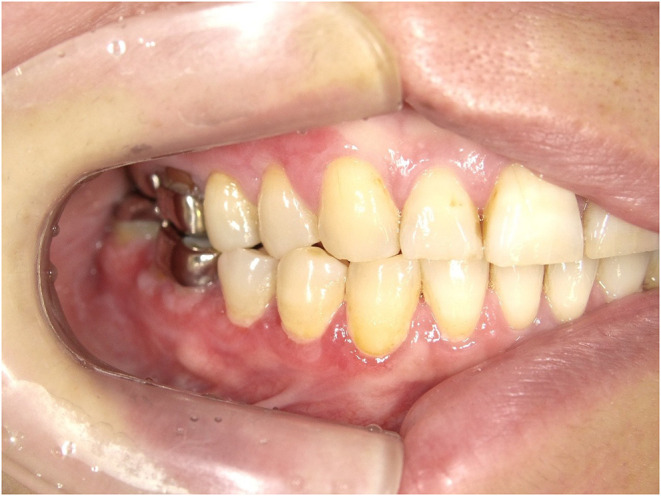

Patients and methods: A 55-year-old female presented with redness and pain near the buccal gingiva of the right mandibular first molar, along with white lace-like patches. Intraoral examination revealed multiple metal restorations, and element analysis identified Zn and Co in several crowns. Based on these findings, a metal allergy was diagnosed. All metal crowns were replaced with zirconia. However, symptoms persisted. A biopsy later confirmed OLP, and steroid therapy was initiated.